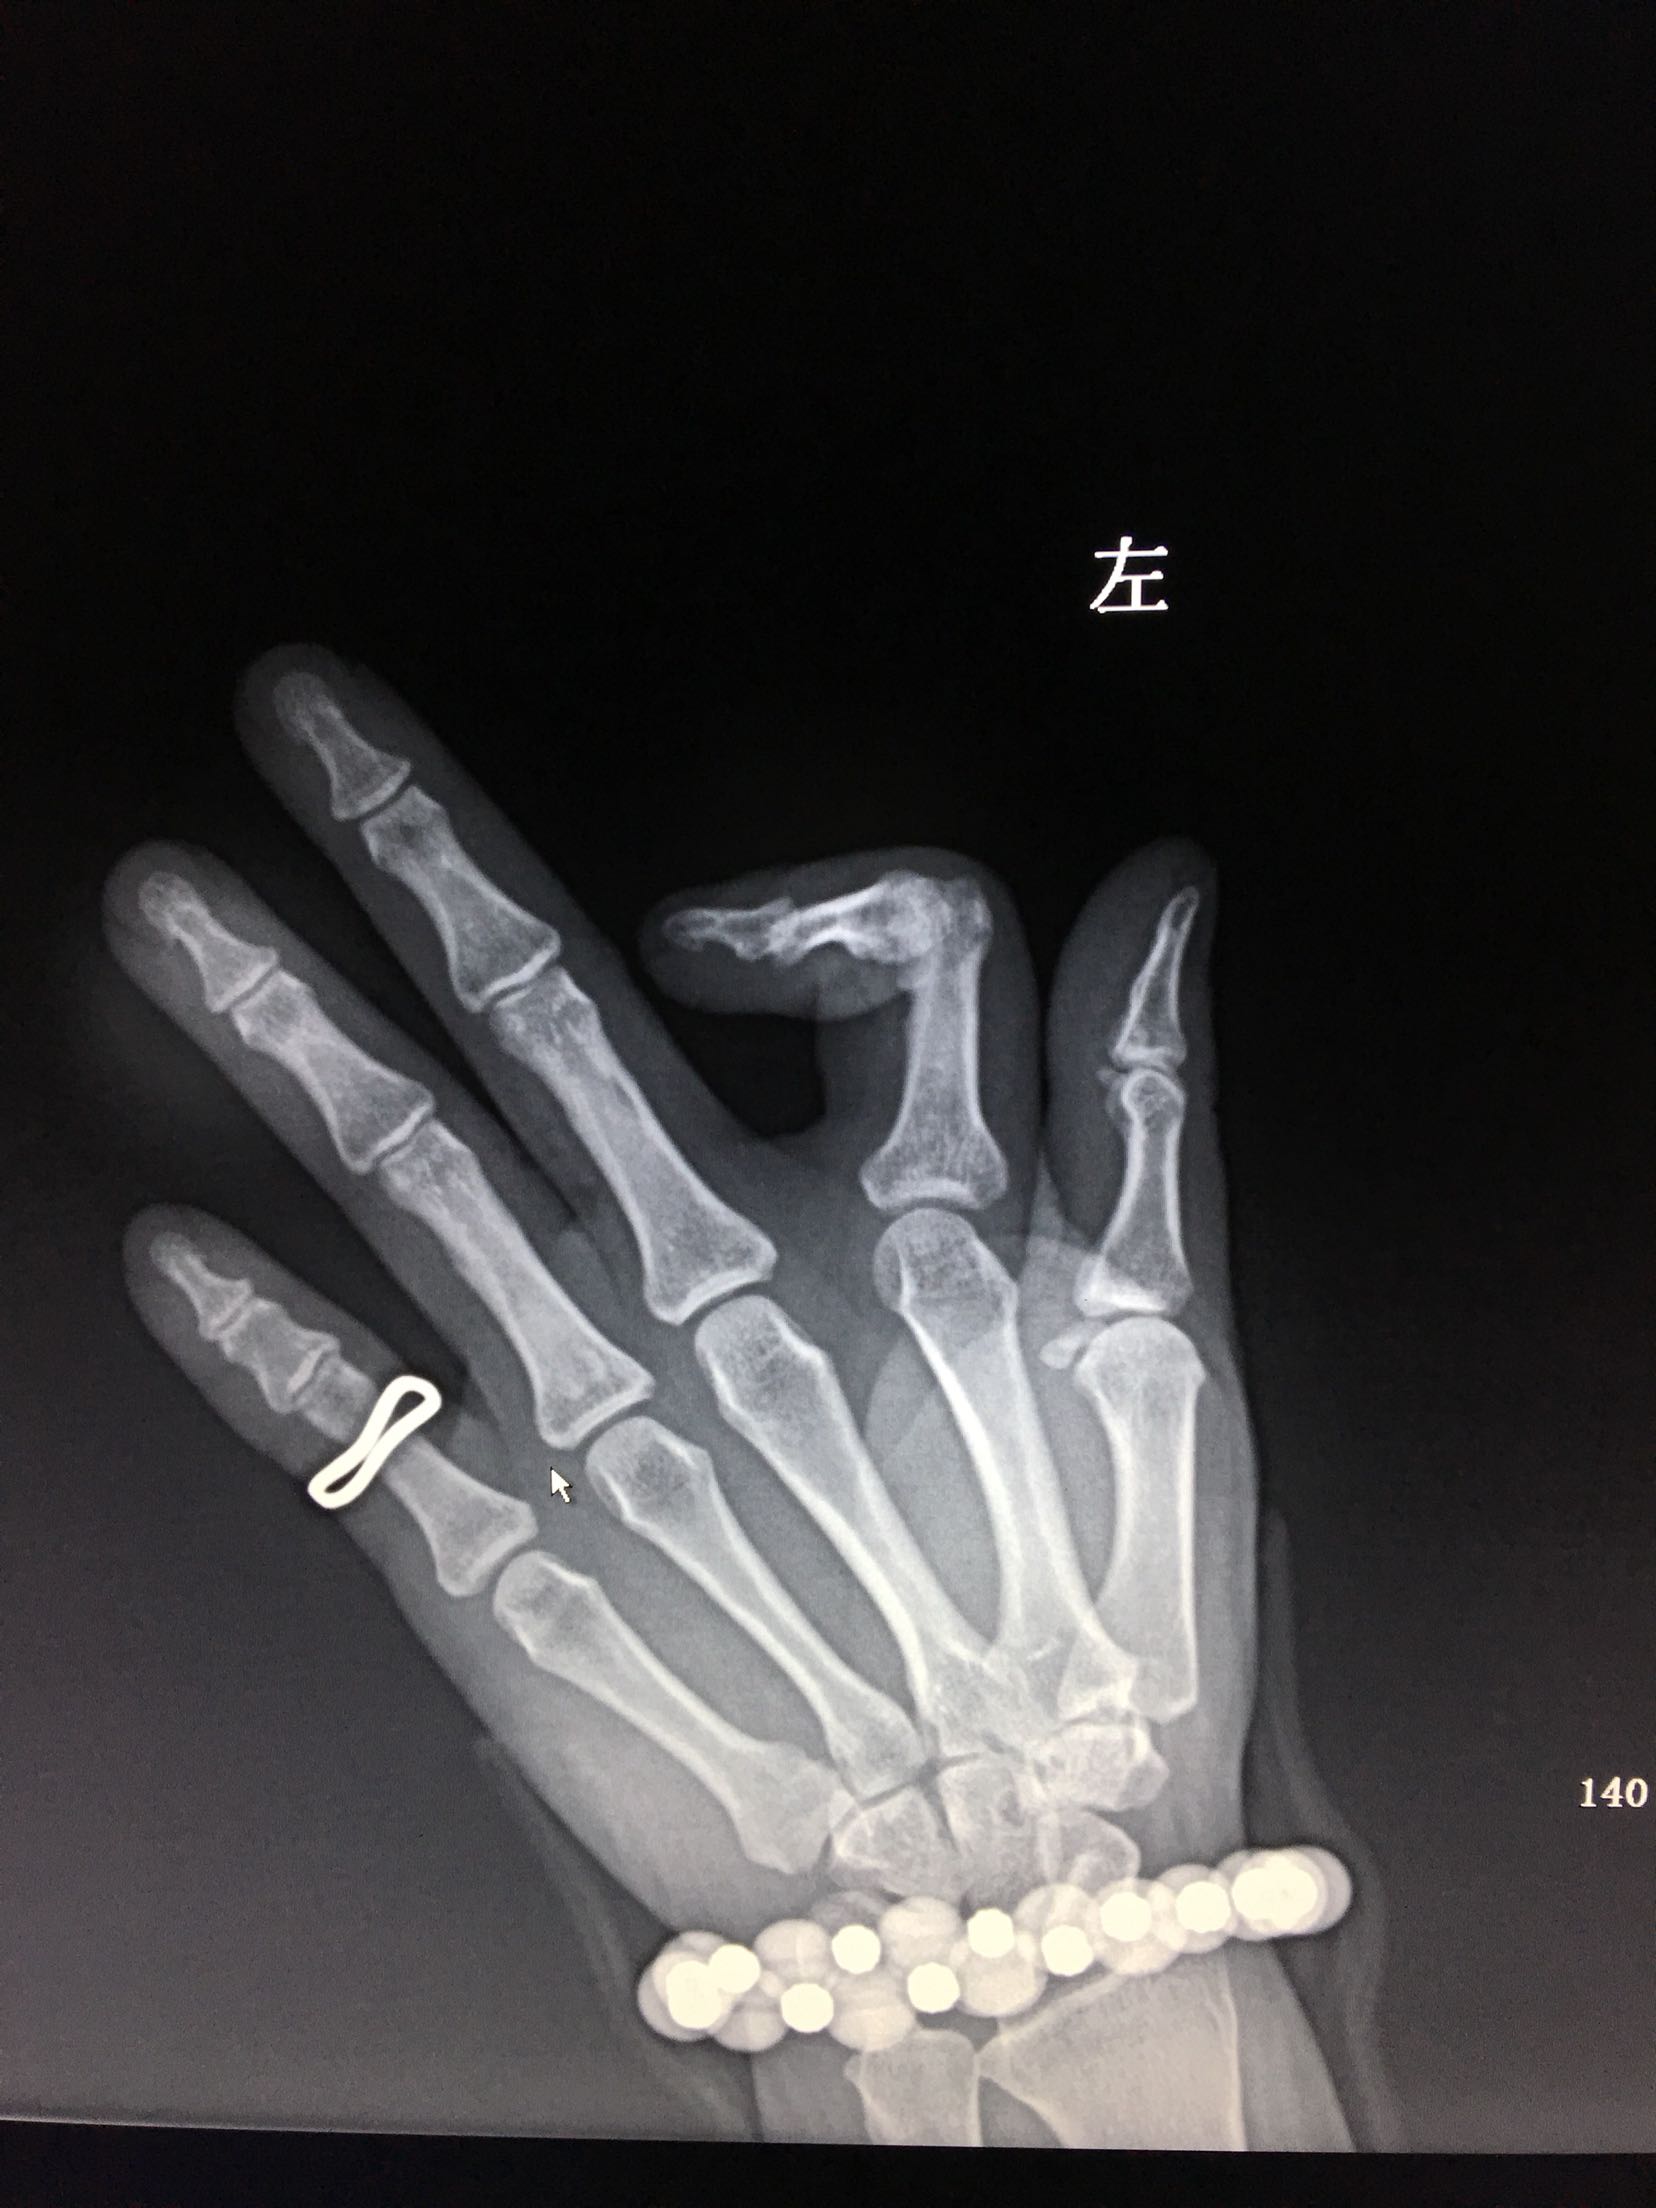

左手食指外伤史现手指畸形